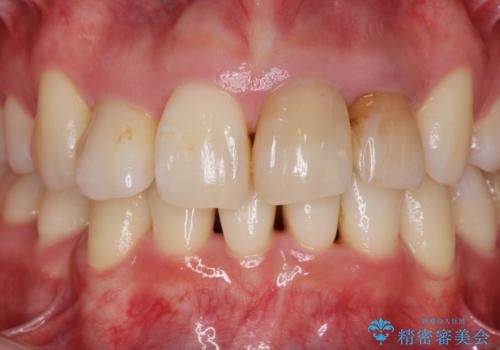

根管治療をしたのち時間が経過して変色が目立つ歯と、レジン充填が複数箇所に及んでいる歯も同時にオールセラミック治療を行っていくこととなりました。

- 52.8万円(ジルコニアクラウン×4・仮歯×4)費用は治療当時の料金となります

自然な歯の色に仕上げることができ、大変喜んでいただくことができました。